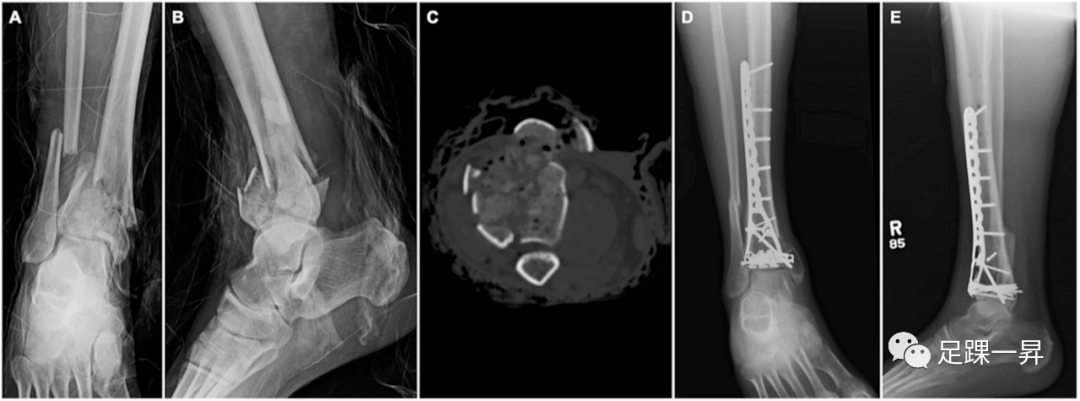

2. 影像学和分型

高能量胫骨Pilon骨折的初步影像学评估包括膝关节、胫骨和腓骨、足和踝关节的标准正侧位X线片。计算机断层扫描(CT)对于评估和术前规划是必不可少的,但在初始骨骼稳定(例如,外固定)或初步复位已经发生,因为韧带复位可以提高对骨折形态的了解。Rüedi和Allgöwer最初将胫骨Pilon骨折分为3种类型,但最近开发的OTA/AO分型系统仍然是最广泛使用的。一些部分关节内(43 B型)Pilon骨折可能发生在高能量环境中,前方撞击可能预示着较差的结局。然而,大多数高能量损伤构成43 C型(完全关节内)。虽然腓骨骨折与OTA/AO型43 C型相比更常见,但它们似乎不能预测43 C型损伤的严重程度。

利用CT扫描对与Pilon骨折相关的主要骨折块进行分类,由此可以制定手术入路。Cole等人评估了38例43C型损伤患者的轴位CT扫描骨折类型,发现所有患者均包含3个主要关节碎片(前部、内侧和后部),标志性粉碎和嵌顿典型地累及胫骨远端中央和前外侧。Topliss等人提出了使用108例患者可进行CT扫描。他们确定了可能发生的8种类型。Leonetti还提出了一种新的基于CT的分类系统。该系统根据关节受累、关节碎片的描述、原发骨折平面和粉碎性分为4种骨折类型。除了评估骨损伤,CT扫描可用于评估周围的软组织包膜。在这方面,Fokin等人回顾了200例43C型损伤患者的CT扫描,发现90.9%的病例有腓骨肌腱移位,86.8%的病例有踝关节后内侧肌腱或胫后神经血管束卡压。如果在手术过程中没有识别或解决,对这些结构的进一步损伤可能会产生有害的结果,并可能影响实现解剖复位的能力。三维CT重建虽然缺乏CT扫描的细节,但提供了一个全局图像,并有助于更可靠的分型和术前计划。

△图示Cole等提出基于轴位CT3个主要骨折块(前部、内侧和后部)。